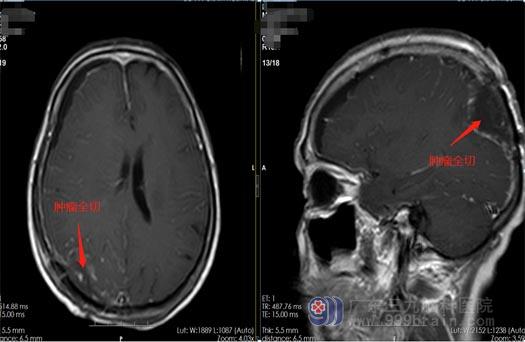

家人找到了广东三九脑科医院鲁明副院长。完善相关检查后,鲁明及神经外五科主任王国良带领治疗团队进行仔细的病历讨论,入院第三天即在全麻下行右侧枕部脑膜瘤切除术,术中镜下全切肿瘤,血管保护完好,手术顺利结束。

术后第二天,祁阿姨视力较前明显改善,术后复查头颅MR结果显示:原右侧枕部脑膜瘤已全切,未见明显残留;术后病理结果显示:纤维型脑膜瘤(WHO 1级)。术后双眼视力恢复良好,第六天办理出院。祁阿姨说之前怎么也没想到脑袋有问题也能影响到眼睛。